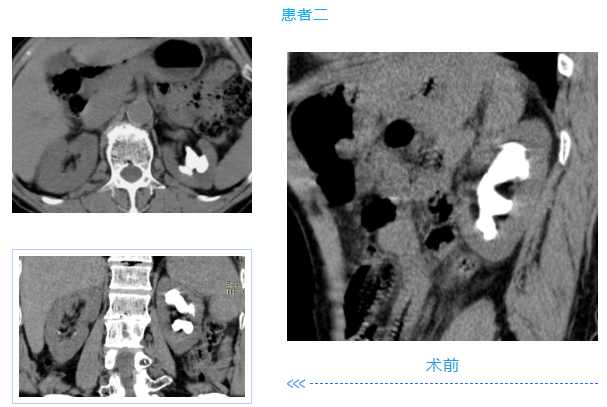

两名患者均为中年男性,入院检查发现肾内多发铸型结石,结石体积大、分布广,其中一例既往患肾行开放取石及经皮肾取石手术,盏颈狭窄伴有肾积水;另一例无明显积水,净石难度高。传统开放手术创伤大、恢复慢,单一微创技术难以彻底清除结石。针对患者病情,泌尿外科团队高度重视,多次组织病例讨论,结合患者身体状况与手术耐受度,最终制定“经皮肾镜+输尿管软镜”联合微创治疗方案。

在泌尿外科团队及麻醉科团队成员密切配合。患者取斜仰截石位,先通过输尿管软镜探查输尿管及肾盂肾盏情况,精准定位结石;随后在超声引导下建立经皮肾通道,置入经皮肾镜,利用钬激光碎石设备将复杂结石击碎成细小颗粒,部分结石因角度问题经皮肾镜无法够到,则通过软镜配合取石篮将结石拖入经皮肾通道口进行彻底清除。整个手术过程创伤小、出血少,术后患者恢复顺利,未出现相关并发症,现已康复出院。